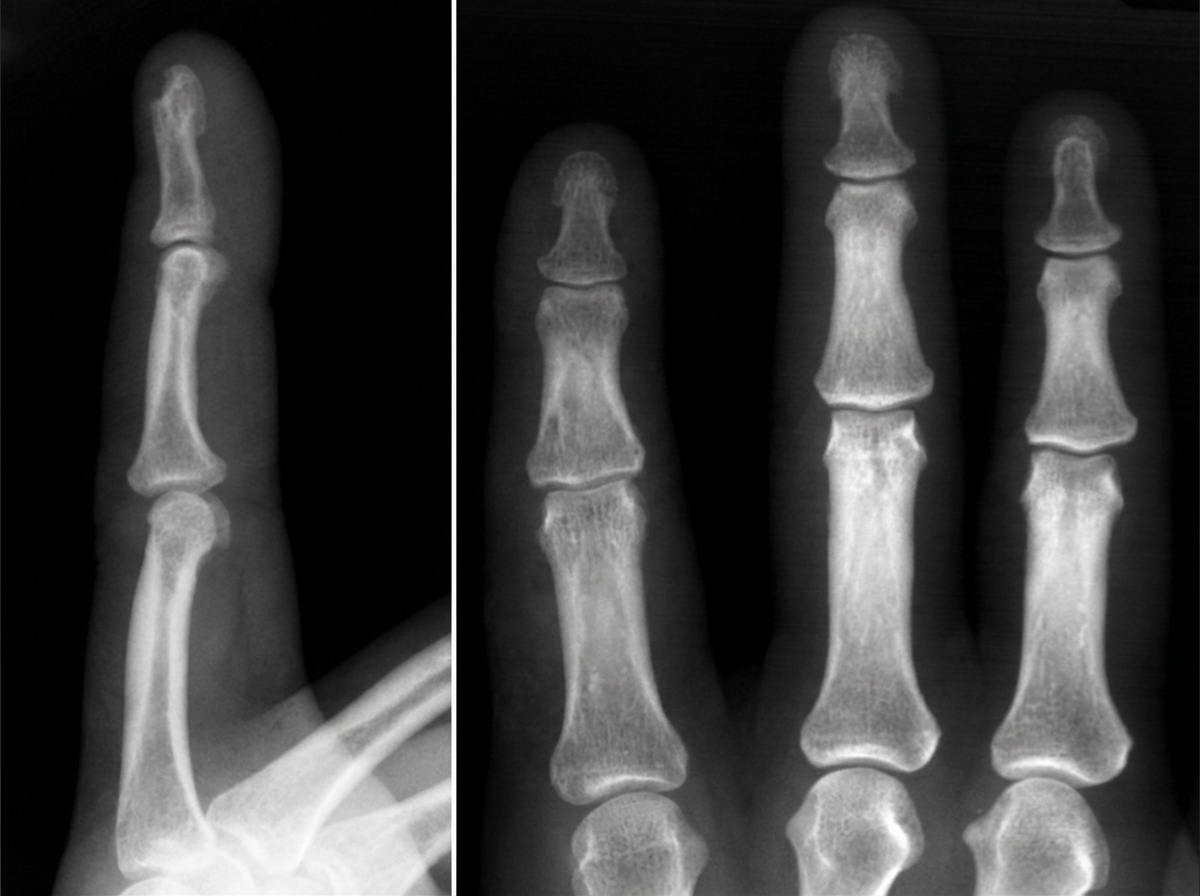

A 76-year-old woman presents to the office with a generalized weakness for the past month. She has a past medical history significant for uncontrolled hypertension and type 2 diabetes mellitus. Her temperature is 37.0°C (98.6°F), blood pressure is 135/82 mm Hg, pulse is 90/min, respiratory rate is 17/min, and oxygen saturation is 99% on room air. Physical exam shows no remarkable findings. Her last recorded glomerular filtration rate was 30 mL/min. A radiograph of the patient’s hand is given. Which of the following lab findings is most likely to be found in this patient?